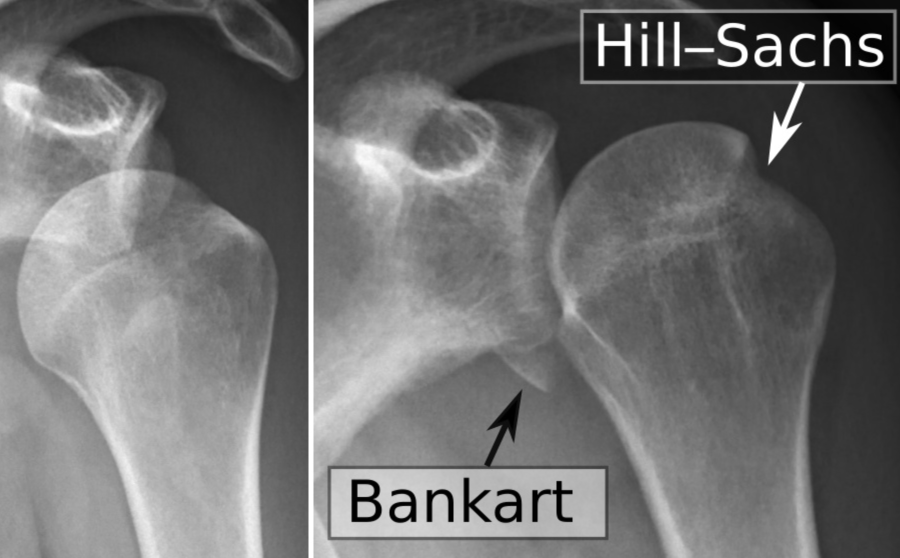

Dislocation Antérieure

- Encoche de Hillsachs (postero-supérieur) (chercher l’ostéocondensation sous-chondrale)

- Bankart Osseux (antéro-inférieur)

A noter que le Hill-sachs se voit mieux sur les incidences RI